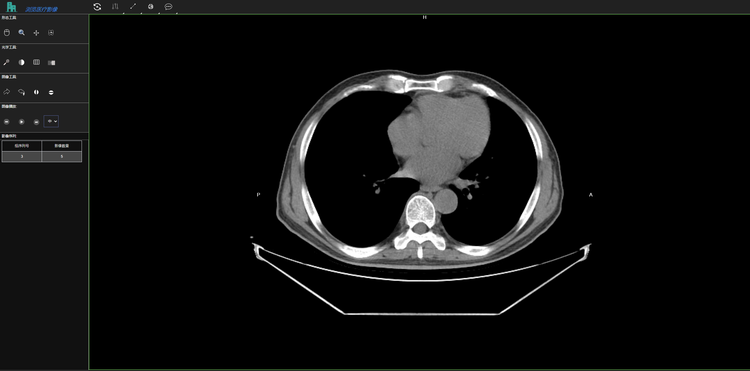

白云医疗影像系统是广州市白云区卫健委推动健全社区-中心医院体系的中间平台。白云医疗影像系统联合中心平台和各个社区医院实现患者影像检查的诊断和会诊功能。从中心平台可得到各个社区医院上传的患者影像数据进行诊断和联合会诊,并将诊断报告返回给中心平台。通过点击患者影像检查单中的AI影像分析按钮,可以跳转至AI影像分析系统上查看该患者的AI影像分析结果。普通影像分析和AI影像分析的结果可以大大地提高医生对患者病情诊断的准确率和效率,加强了各级社区医院与中心医院主治医生的交流与合作,均衡了各级医院医生资源,为广大患者带来更多便利。

为医疗影像提供了一种针对docom格式的图片文件的标注工具和存在方式。为不同医院的医生搭建远程会诊桥梁,实现AI阅片。